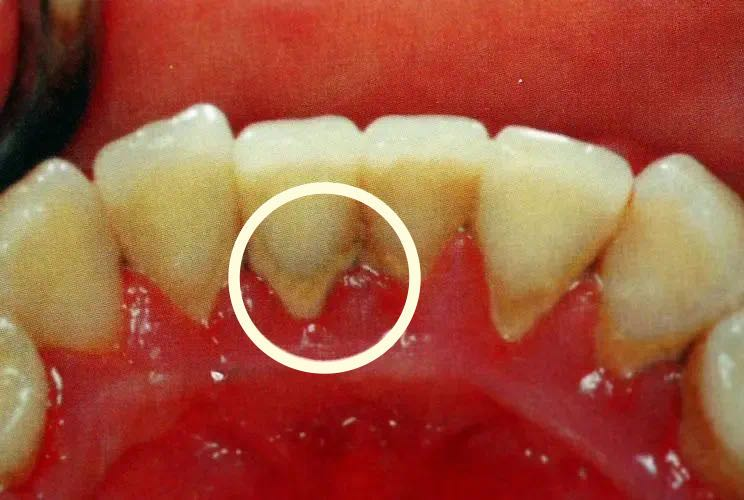

久而久之,牙菌斑越积越多,形成牙结石,寄居在牙结石上的细菌会产生酸性物质,开始逐步破坏我们的牙齿,刺激牙龈,造成牙齿敏感疼痛、牙龈肿痛出血,这便是牙周炎的早期症状。

久而久之,牙结石越堆积越多,牙周炎症越来越严重,牙龈肿痛、牙齿疼痛加重,这时很多人会用消炎药、止痛药来应对,结果问题越来越严重,牙龈逐渐萎缩,牙槽骨也随之吸收萎缩,牙根失去充足的支撑,牙齿开始松动、摇晃。

牙齿松动疼痛是牙周炎的主要症状。而牙菌斑牙结石又是牙周炎症的始动因素。因此,解决牙齿松动疼痛问题的关键,就是要清除牙菌斑牙结石。